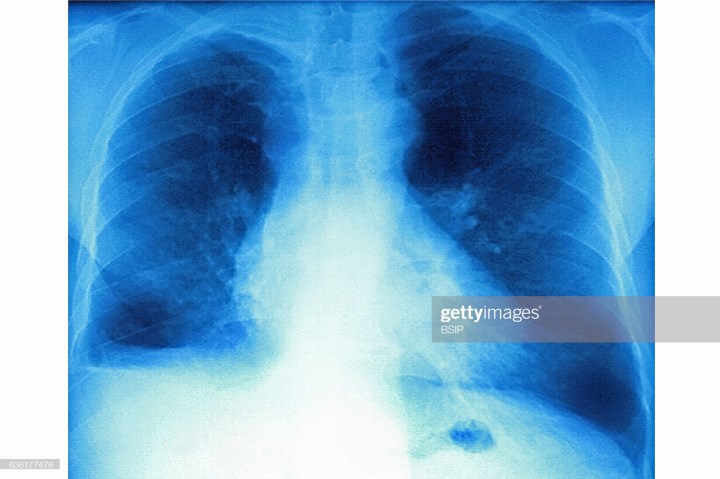

- Image Retrieved from: https://www.gettyimages.com/detail/news-photo/mucoviscidosis-seen-on-a-frontal-x-ray-of-the-chest-news-photo/636177476?adppopup=true